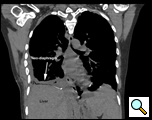

Figure 8: Postoperative chest CT scan reveals neo-diaphragm and reduction of the liver back into the abdomen. |

She made an uneventful recovery and was discharged on postoperative day seven. Pathologic examination of the liver revealed normal liver parenchyma with no diagnostic abnormality. The visceral and parietal pleural biopsies revealed chronic pleuritis. A postoperative CT scan revealed an intact diaphragmatic repair with the liver within the abdomen and the right lower lobe completely expanded (Figure 8). Patient has been seen in our clinic approximately 3 months following surgery with no recurrence of hepatic herniation, improved effort tolerance and no recurrence of her loculated effusion.